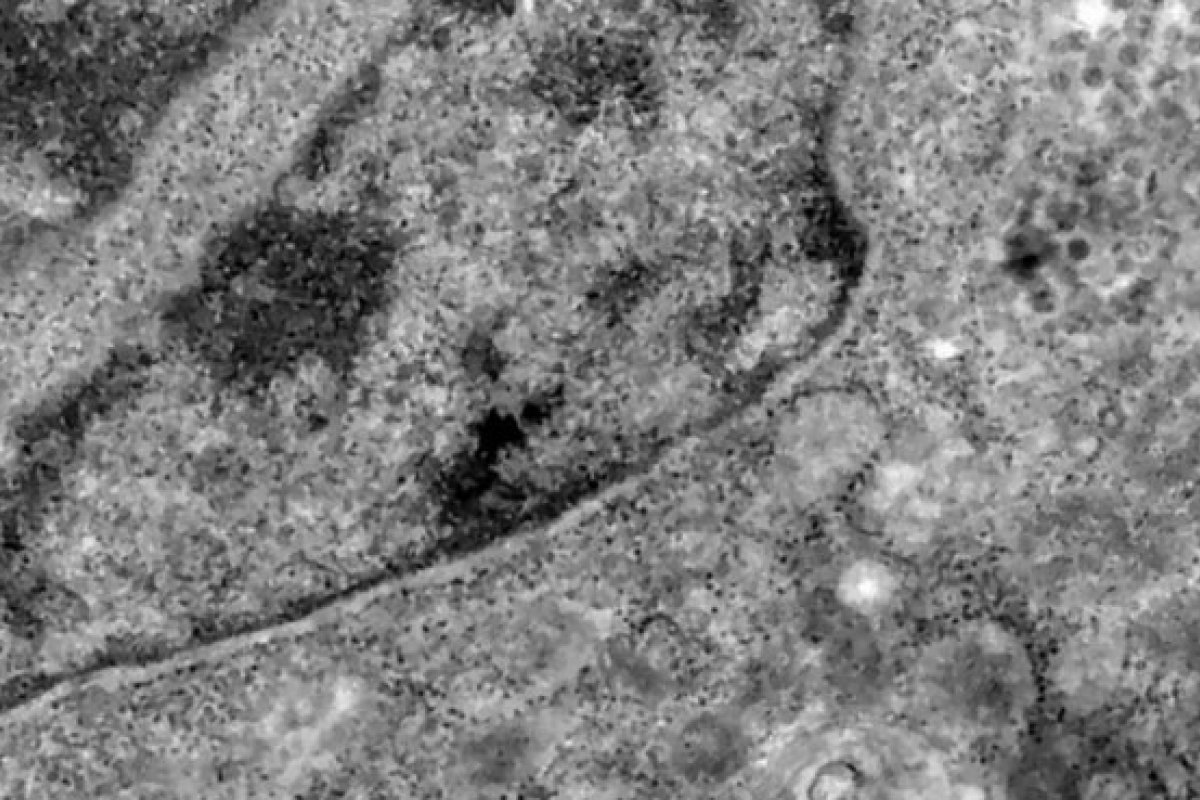

Foto: Divulgação/Fiocruz

Uma pesquisa realizada por cientistas brasileiros da Universidade Federal de São Paulo (Unifesp) e Universidade Federal do Rio de Janeiro (UFRJ) conseguiram, pela primeira vez, detectar o coronavírus em retinas. Com esse estudo, os profissionais poderão compreender melhor a dinâmica do vírus e as sequelas em pacientes infectados.

O estudo analisou retinas de pacientes que morreram em decorrência da covid-19 e compararam com fotos dos olhos desses pacientes quando vivos para analisar as diferenças e formas de aferir a presença do vírus a partir da retina.